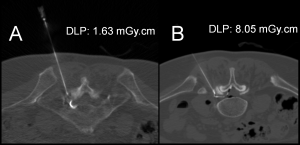

The needle tip visibility did not differ significantly between the two groups (p = 1.0, Chi-square test) (Figures 2, 3, 4, and 5). The needle tip was visible in nearly every patient in this study (170 out of 171).